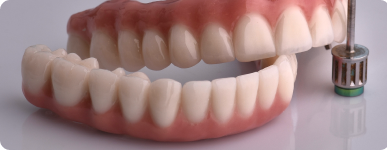

Delimična bezubost i bezubost:

Kada pacijentu nedostaje više od 10 zuba ili ako zubi gube stabilnost zbog paradentoze, koristi se ALL ON 6 implantsko rešenje. Ono podrazumeva vađenje preostalih zuba, ugradnju šest implanata po vilici i šrafljenje trajnog titanijumsko-keramičkog rada na implantima.